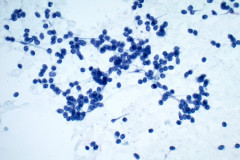

Cytology:

Aspirates of MTC are moderately cellular, showing a single cell pattern with occasional clustering and small aggregates. Cytologically, tumor cells can appear plasmacytoid, polygonal, or with spindle cells. Cells are uniform in size, but rare large pleomorphic cells may be present. The chromatin shows a coarse, granular, neuroendocrine pattern with inconspicuous nucleoli. Intranuclear inclusions may be seen, and nuclear grooves are rare. The cytoplasm is granular, and the amount is variable and rarely scant. Cytoplasmic dendritic processes may also be seen. Amyloid may be present in the background, although it can be identical to colloid in Papanicolaou-stained specimens. Variants of MTC include a follicular variant, papillary variant, small cell variant, giant cell variant, and a clear cell variant7. Cell blocks of MTC typically stain positive for calcitonin, CEA, TTF1, synaptophysin, and chromogranin, and are negative for thyroglobulin and PAX-88,9.

The tumor cells of this case presentation posed a diagnostic challenge due to their divergence from the typical cytological appearance of MTC. The majority of tumor cells had scant cytoplasm, including cells that resembled naked nuclei and cells with a plasmacytoid appearance. A diagnosis of MTC was rendered in conjunction with the patient’s elevated calcitonin level, history of MTC and MEN2, and comparison to the patient’s previous two MTC diagnoses.